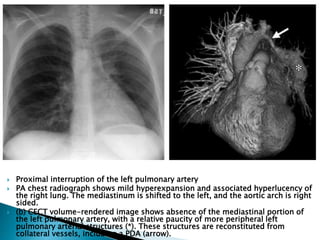

 Proximal interruption of the left pulmonary artery

 PA chest radiograph shows mild hyperexpansion and associated hyperlucency of

the right lung. The mediastinum is shifted to the left, and the aortic arch is right

sided.

 (b) CECT volume-rendered image shows absence of the mediastinal portion of

the left pulmonary artery, with a relative paucity of more peripheral left

pulmonary arterial structures (*). These structures are reconstituted from

collateral vessels, including a PDA (arrow).